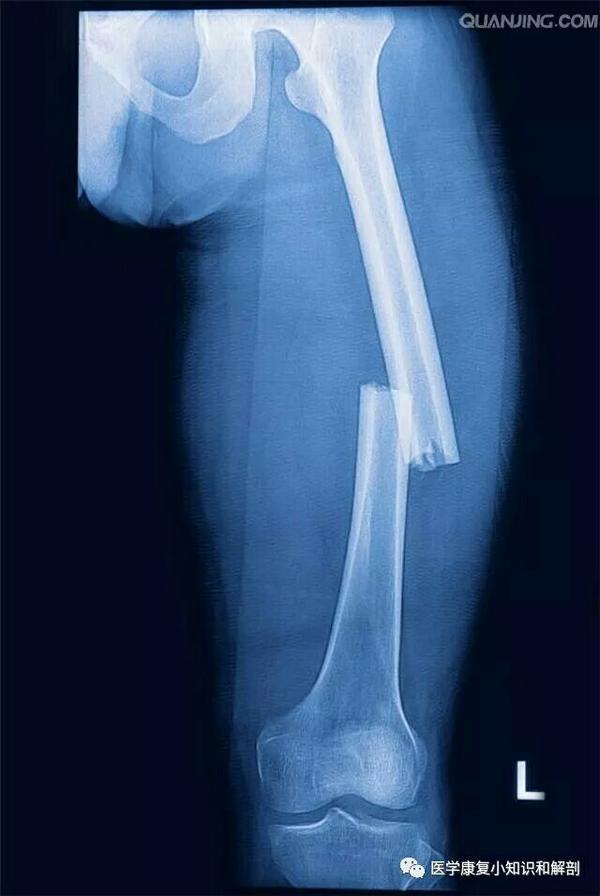

骨組織の基本構造 骨幹 骨幹端 骨端 皮質骨 海面骨 トレーニング Univ

骨の真ん中の部分。 厚い緻密質で構成され、内部に骨髄を入れる。 海綿質 長骨の骨端や椎骨などの骨の内部はスポンジ状の骨梁があつまり海綿質と呼ばれる。 緻密質 骨の表面近くで骨組織だけでできている部分。 腱や靱帯の付着部分では厚さが増す。 ※ 骨の表面は骨端の関節面を除いてすべて結合組織性の骨膜でおおわれています。 骨膜は血管骨の内側は、スポンジ状の 海綿質 となっている。 海綿質と緻密質によって、大きな力であっても、少量の材料で支えることが可能である。また、海綿質は 骨稜 によって構成されている。骨稜は、力かかかっている方向に対応して配列を行う。 長い骨(長骨幹は緻密質(緻密骨)が発達しており、海綿質はほとんど見られない。骨端は緻密質は薄く、内部に海綿質が発達している。 3.骨梁シャーピー繊維 誤り。 骨梁(こつりょう)は、海綿質を作っている、骨でできた小さな梁(はり)(あるいは小さな柱

骨の緻密質(緻密骨)と海綿質(海綿骨)の構造 骨質は表層を占める 緻密質(緻密骨) と内部を占める 海綿質(海綿骨) とからなる。 骨質(緻密質・海綿骨)は、骨細胞および基質(規則性をもって走る膠原線維とその間を満たすリン酸カルシウム、炭酸カルシウムなどの無機質)で構成されている。

長骨の内部構造 思春期に身長が伸びる仕組み Hanalima ハンドメイド教材の部屋